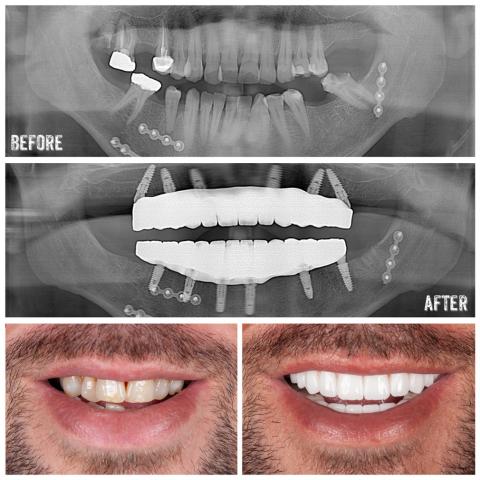

Dental Treatments